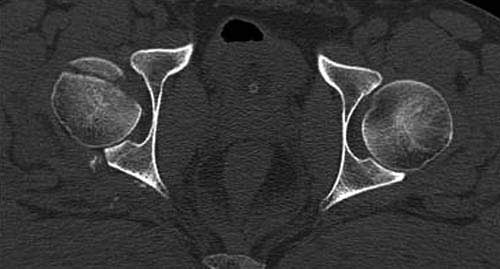

Представлены несколько вариантов фиксации: первый случай перелом головки с задним краем, операция из заднего доступа Кохер, а второй случай изолированный перелом головки - из трохантерного доступа.

Имя     : 3 Fem head  CT.jpg

Тип     : image/jpg

Размер  : 27916 байтов

Описание: отсутствует

Url     : http://weborto.net:8080/pipermail/ortho/attachments/20111231/d311d17a/attachment-0017.jpg